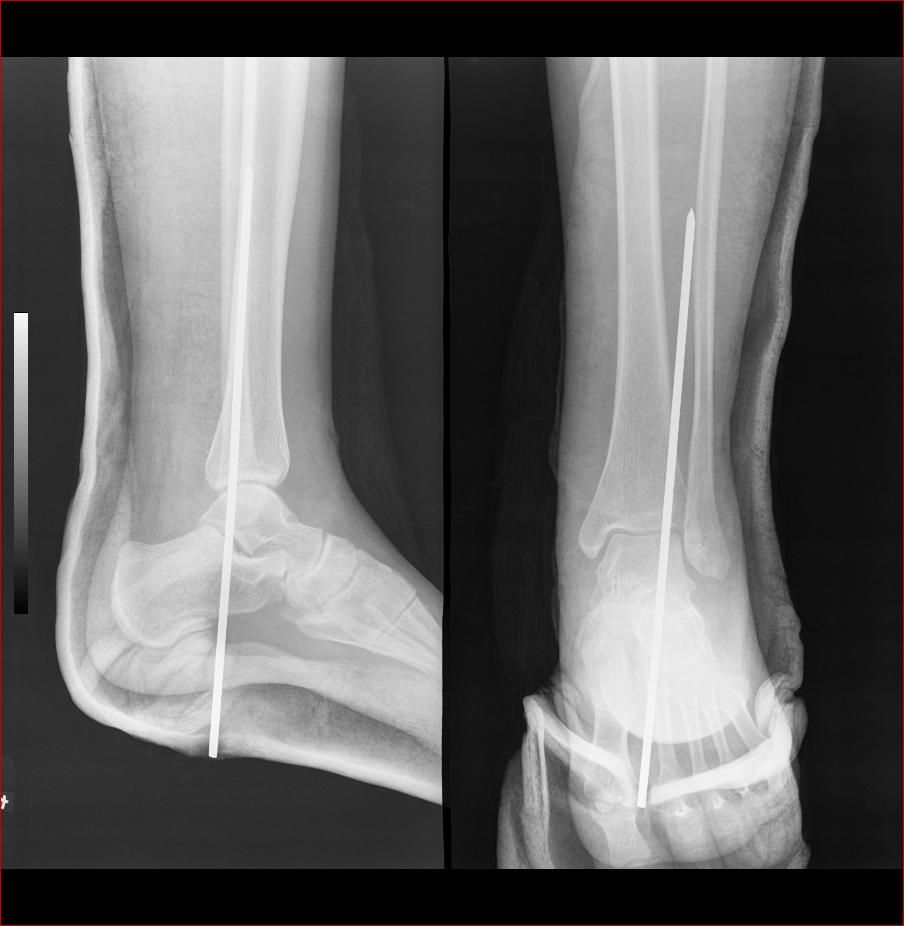

术后片: